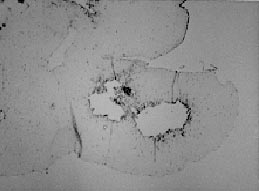

Endometric organotypic culture demonstrating cavity formation inside of the collagen. The cavity is lined with epithelium and only cells with fibroblast morphology are observed inside the collagen.